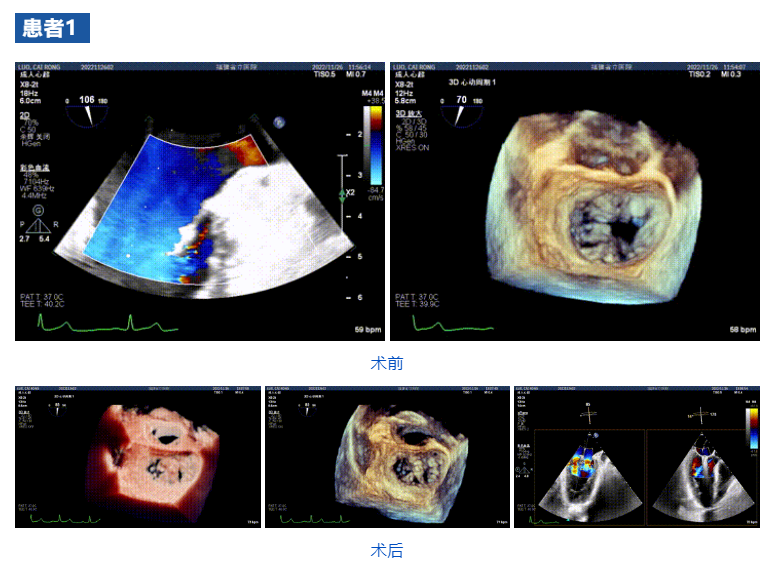

接受治療的三例患者均為器質(zhì)性重度二尖瓣反流(DMR)患者,術(shù)前超聲提示二尖瓣后葉脫垂伴4+反流,左室舒張功能減退。郭延松教授攜同團(tuán)隊成員陳新敬副教授和洪景宣、方明程、楊清勇主治醫(yī)師、心外科丁杭主任以及超聲科賴寶春、葉振盛主治醫(yī)師共同進(jìn)行病情討論??紤]到患者高齡、基礎(chǔ)疾病多、STS評分高,為外科手術(shù)極高?;颊?,不適合進(jìn)行外科開胸二尖瓣手術(shù),因此決定為患者實施經(jīng)導(dǎo)管緣對緣修復(fù)介入術(shù)(JensClip經(jīng)導(dǎo)管瓣膜夾系統(tǒng))。

在浙江大學(xué)醫(yī)學(xué)院附屬第二醫(yī)院王建安教授團(tuán)隊的支持下,手術(shù)經(jīng)股靜脈-房間隔入路,采用全身麻醉插管,在TEE和DSA引導(dǎo)下完成房間隔穿刺。置入JensClip瓣膜夾系統(tǒng)后,在左房調(diào)整瓣膜夾的位置和軸向,后進(jìn)入左室,在TEE引導(dǎo)下捕捉二尖瓣前后瓣葉,并關(guān)閉瓣膜夾。經(jīng)TEE反復(fù)確認(rèn)手術(shù)效果后最終鎖定并釋放瓣膜夾。術(shù)后即刻超聲顯示瓣膜夾位置穩(wěn)定,功能良好,二尖瓣反流由術(shù)前4+減少至微量,手術(shù)圓滿成功。